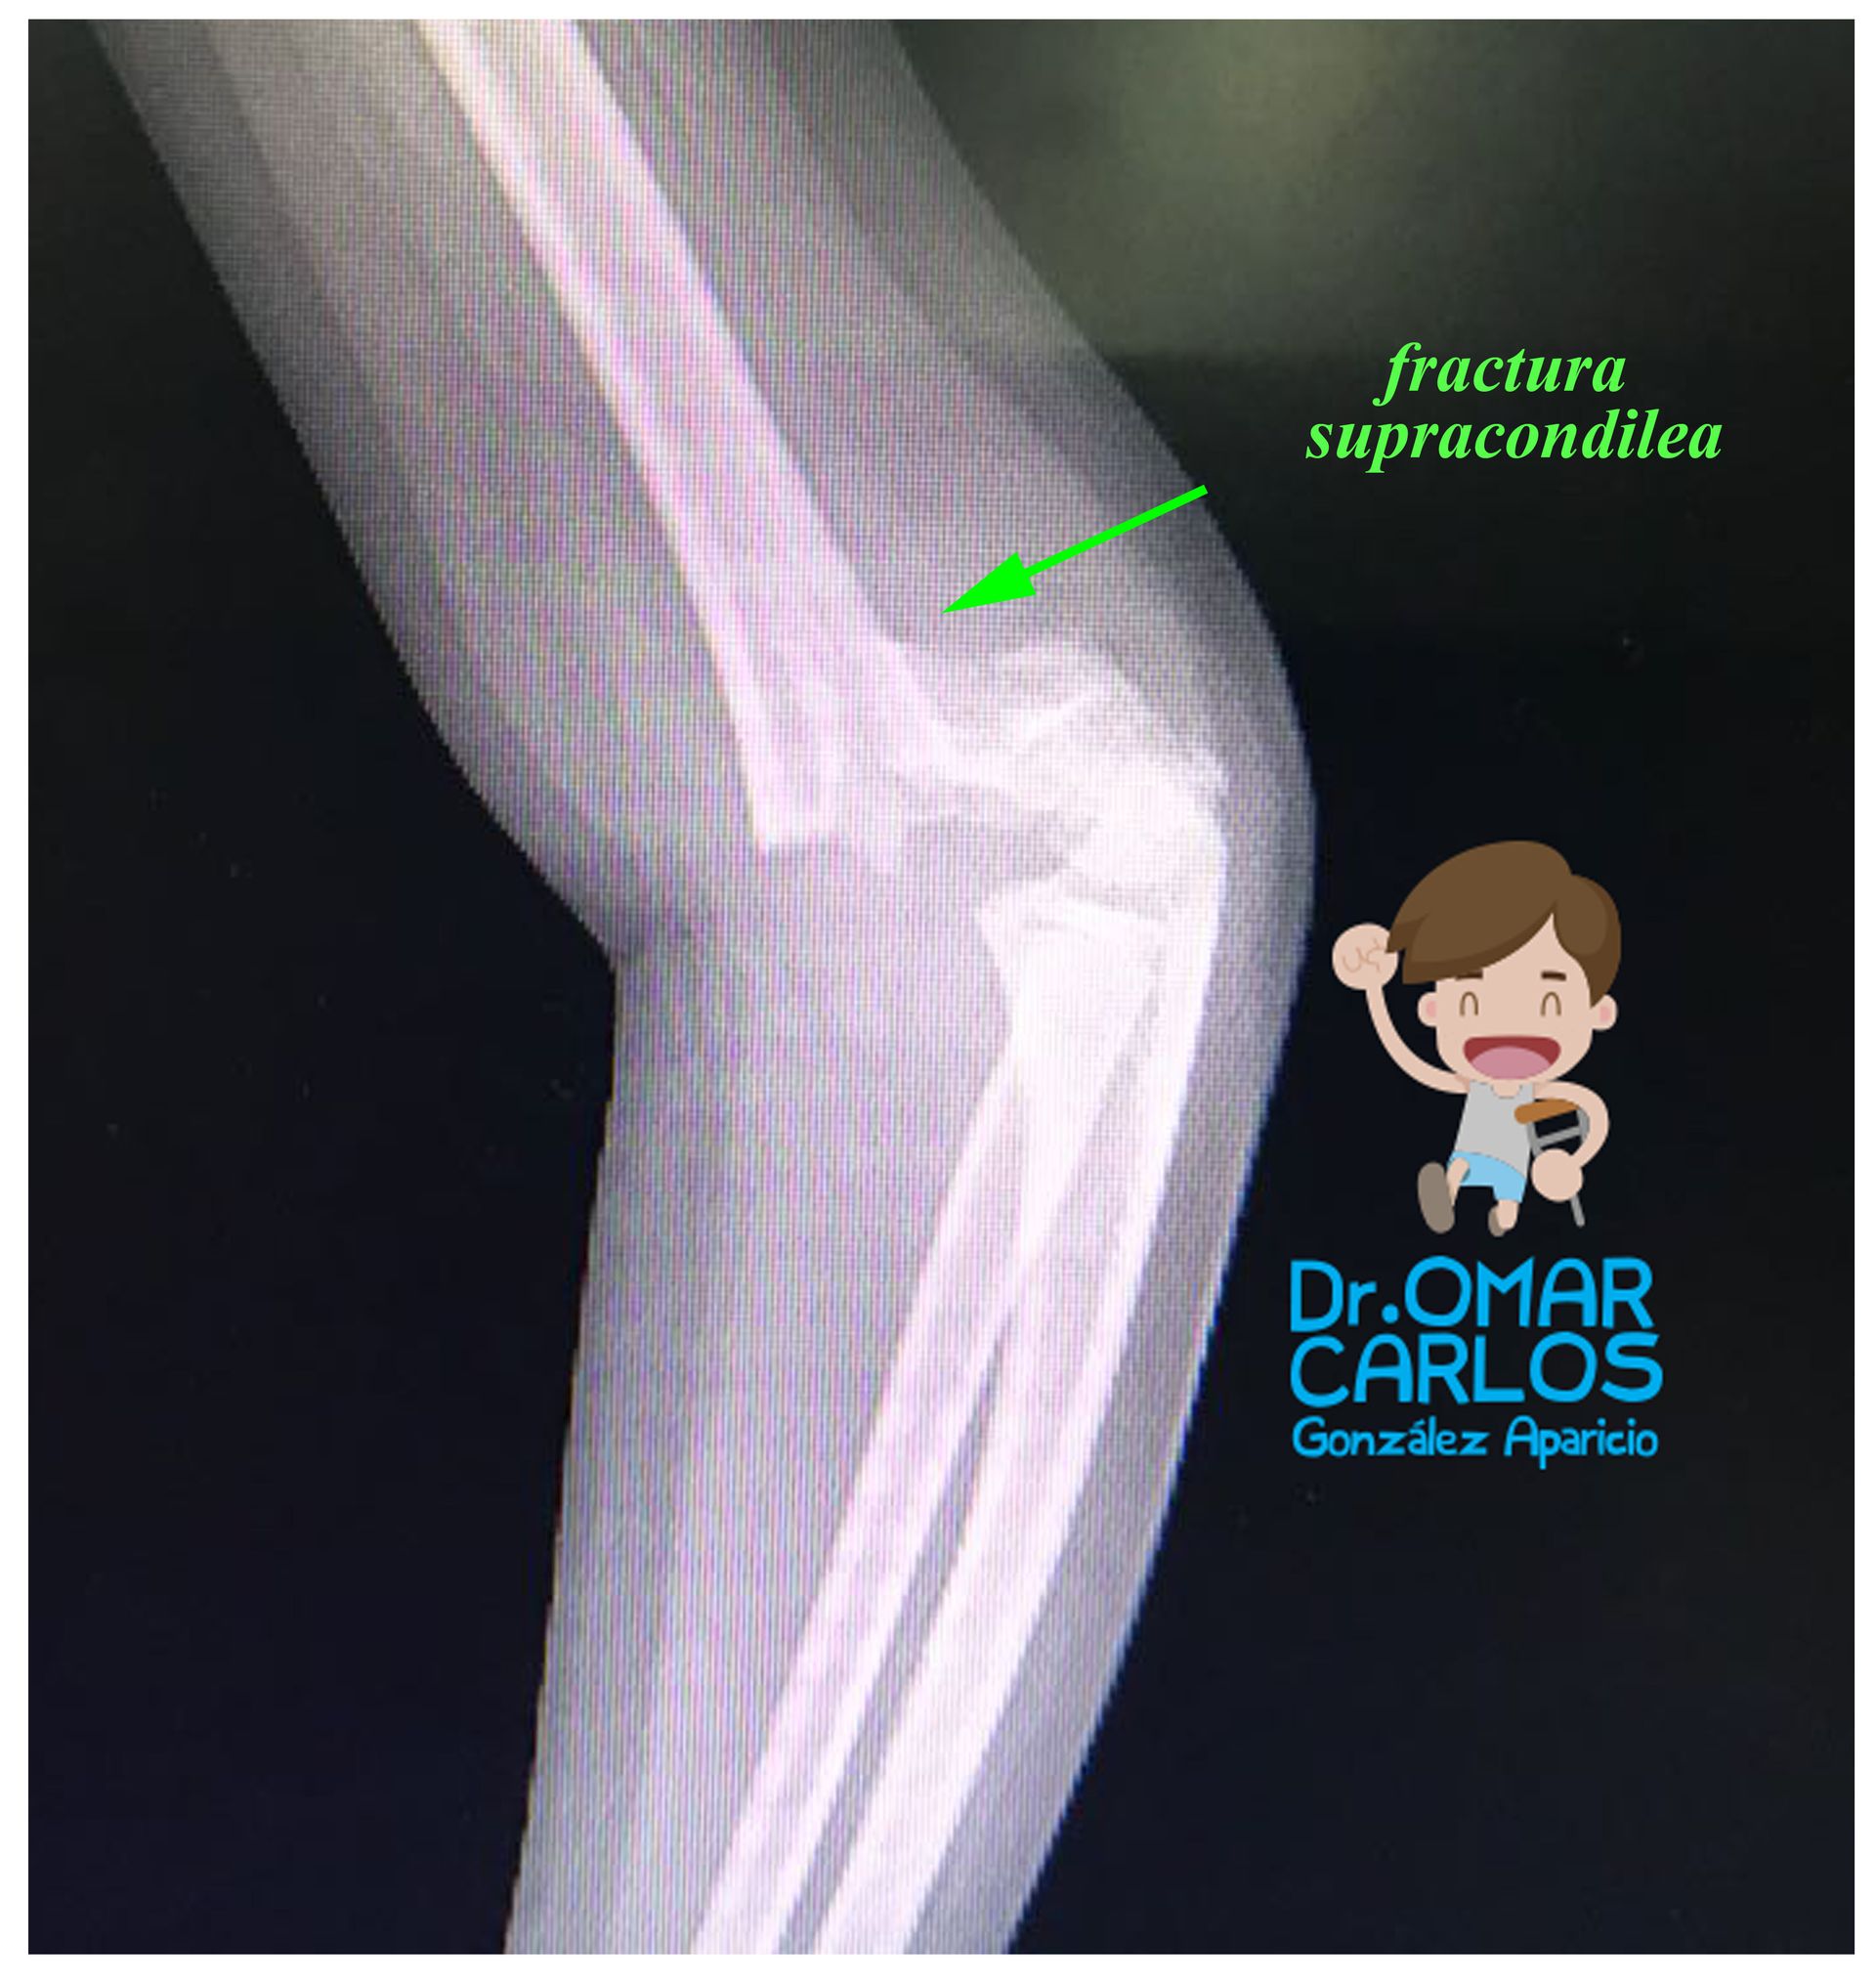

Fracturas supracondileas de humero

Les comparto resultados de fractura supracondilea humero derecho tratada con reducción cerrada + estabilización con clavos.

Las fracturas no desplazadas o con desplazamiento mínimo pueden ser tratadas en forma conservadora (con inmovilización con aparato de fibra de vidrio), pero cuando el desplazamiento es grave o existe rotación, o compromiso vascular o nervioso, debe ser manejada en forma quirúrgica y estabilizada con clavillos.